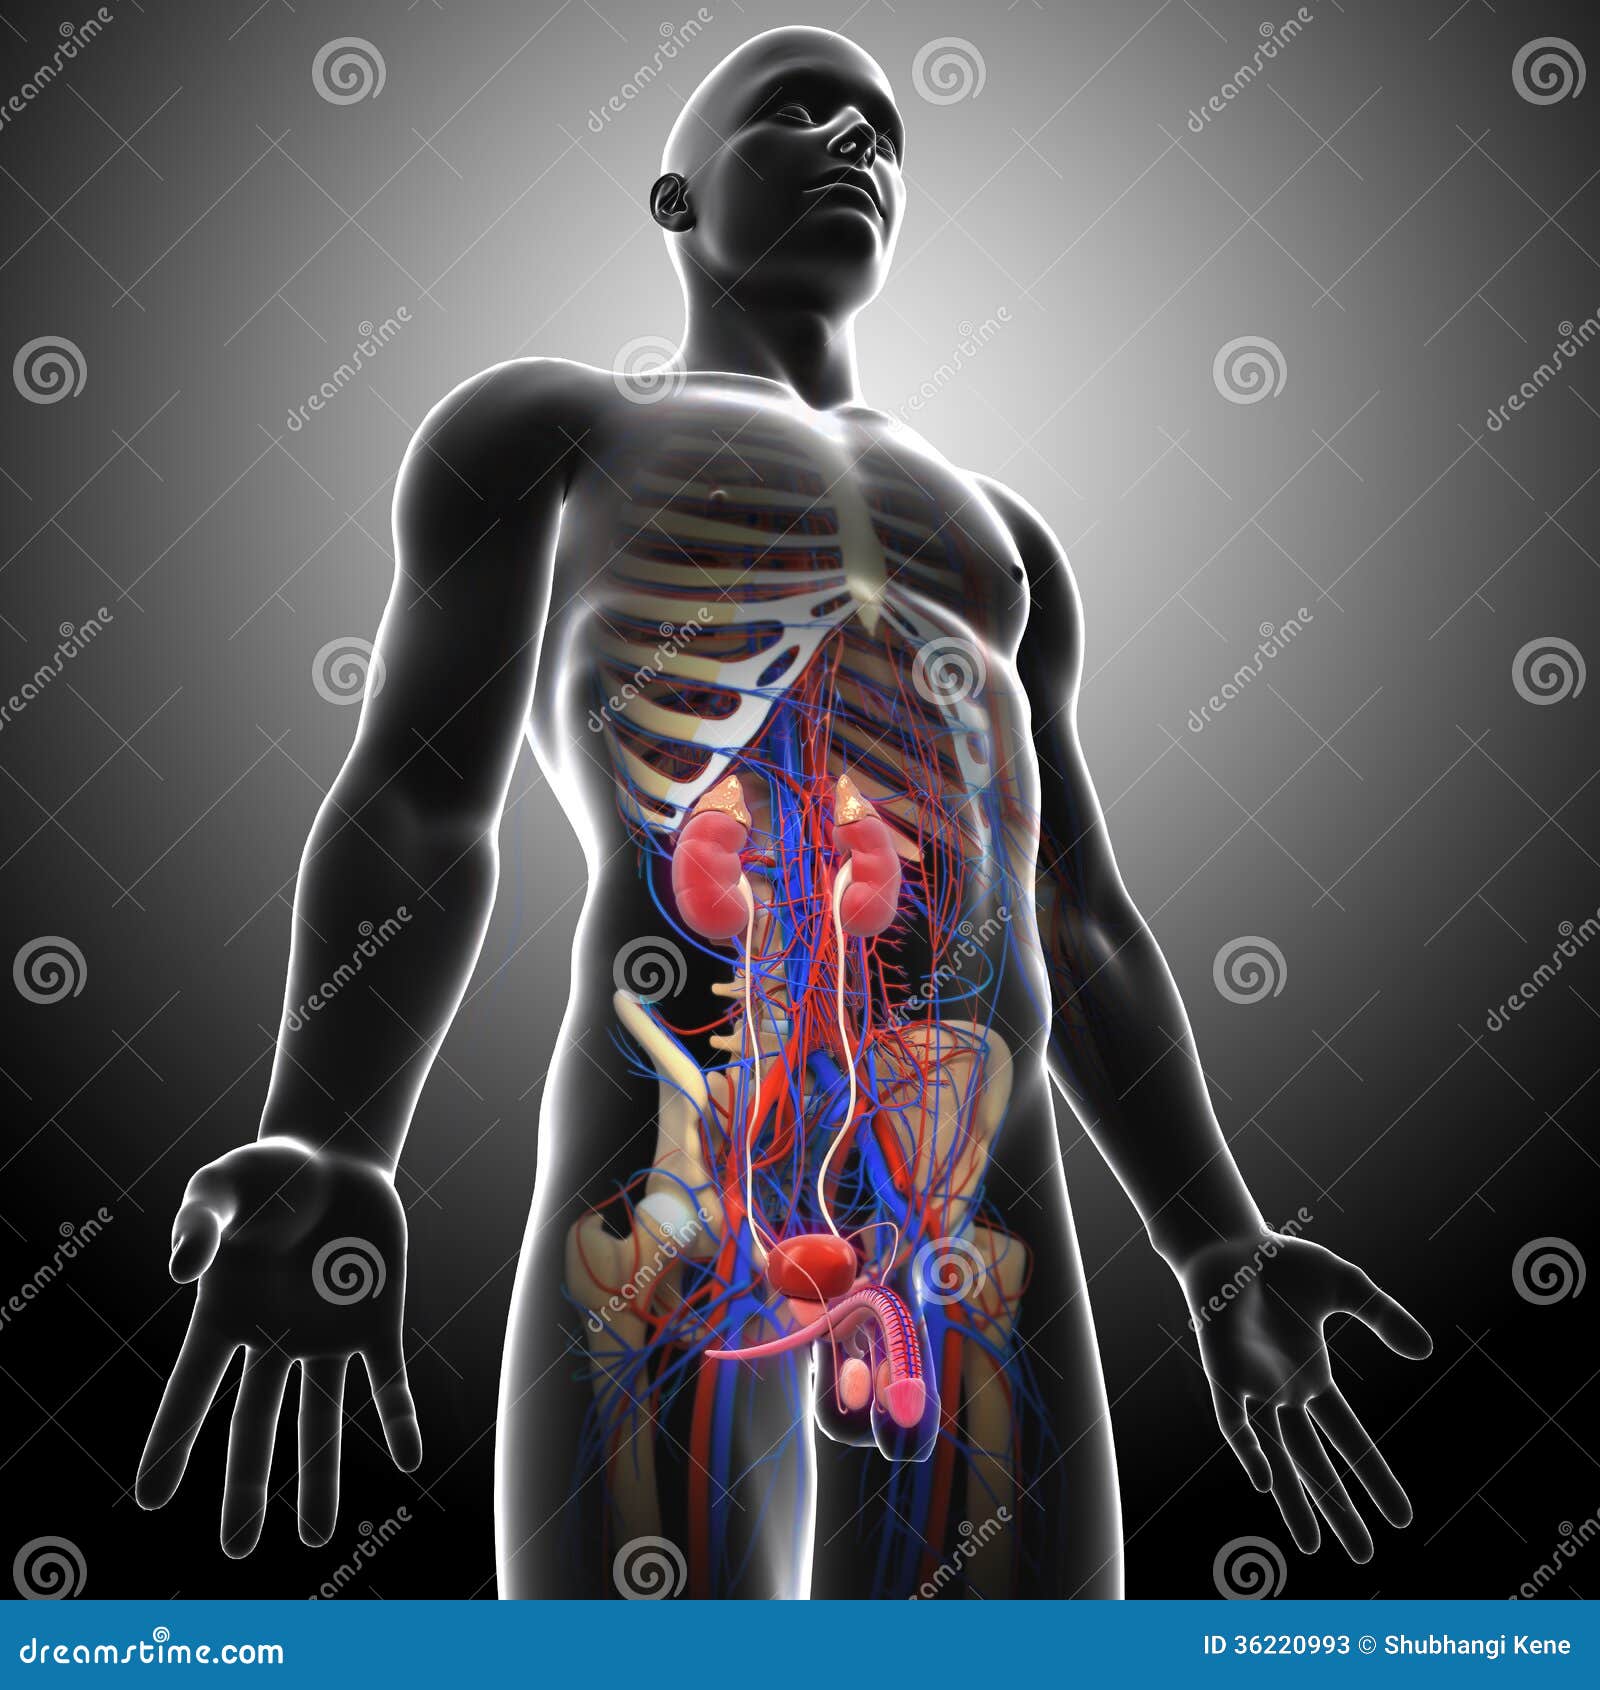

Diagram Of Prostate Background Stock Photos, Pictures & Royalty-Free …

Urinary Tract Anatomy Pictures, Images and Stock Photos – iStock

Human Urinary System In Gray Xray Stock Photo – Download Image Now …

Side View Of Human Urinary System In Gray X-ray Stock Photos – Image …

Female Urinary System Royalty Free Stock Photo – Image: 36221015